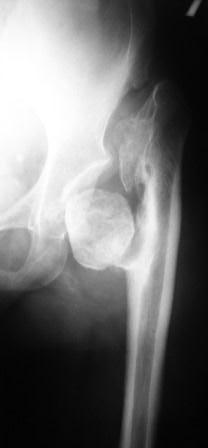

Хотелось бы услышать Ваше мнение по лечению больной 45 лет. Никаких медицинских документов нет. Со слов больной лечили по поводу врожденного вывиха бедра. В 1985г. остеотомия нижней трети бедра и удлинение в аппарате Илизаровна 5см. В настоящее время укорочения конечности нет. Обратилась по поводу выраженного болевого синдрома, который усилился в течение последних двух лет. Судя по рентгенограммам - имел место coxa vara coli lisis с патологическим вывихом бедра. Любое низведение бедра даст грубое удлинение конечности. остеотомии в условиях головки-секвестра мне кажутся бесперспективными.

Где Вы их таких находите? Вариант - эндопротезирование в два этапа: Первый -

чаша с реконструкцией вертлуги и работой на неартрозе выше крыши (убрать его, и слайдинг или даже сегментарная остеотомия вертела или ниже его с низведением и фиксацией). Потянуть бедро вниз аппаратом. Возможно первым этапом бедро не трогать а просто переудлинить. Второй этап - ножка и головка и длина и оставить фиксацию в аппарате? если надо. Четко рассчитать длину

ног - снимки таза всего с нижними конечностями - тогда можно планировать разного типа сечения. Трудности на обоих этапах и риски всякого рода высоки.

Согласен с Вами, что остеотомия бесперспективна.

Мы в подобных случаях отсекаем вертельную область, удаляем промежуточный участок подвертельной области, длиной равной выполненному ранее удлинению и выполняем установку бесцементной ножки.

Для этого хороши новые бесцементные ножки CDH от Biomet, хотя подойдет практически любая бесцементная ножка с дистальной фиксацией.

Важно провести очень тщательное предоперационное планирование и не резецировать больше, чем нужно.

Толя, Здравствуй, Рад встретить тебя - давно не общались,

На АСАМИ в Петербурге в мае 2008 было несколько презентаций с хорошими функциональными результатами после правильно выполненных опорных остеотомий бедра. Поэтому возникают сомнения о целесообразности протезирования в данном случае, но не из-за технических сложностей, а ввиду постоп. функциональности результата: состояние ротаторов, их активность и длина оставляют желать лучшего, судя по Рг. Из сообщения Леонида Полляка следует, что больная страдает от нарастающих болей (при такой анатомии объем движений

должен быть ограниченным и похоже, что сама больная к этому адаптировалась) - всё, что ей нужно - это безболезненная опора на ногу, конечно, хотелось бы и объём движений, но терзаюсь сомнениями,что даже после технически сложной артропластики и красивой послеоперационной Рг картинки гарантировать мобильность и стабильность сустава из-за состояния мышц сложно, а уж Тренделенбург будет обеспечен, с соотв.походкой, риск ранней ревизии? Как ты относишься к этому?